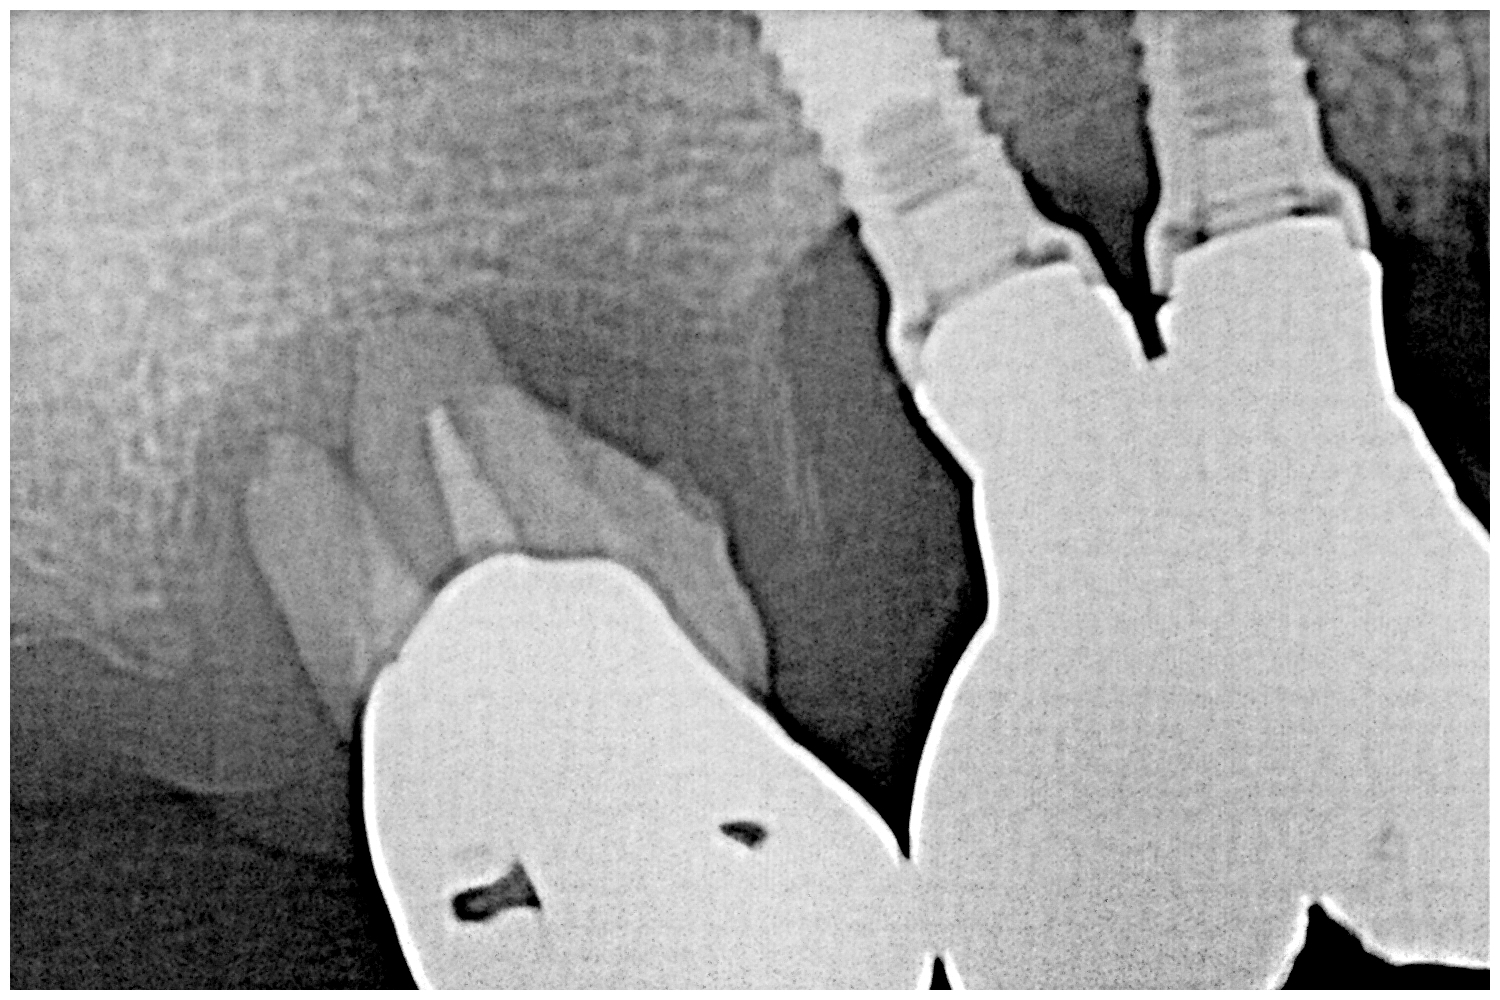

術前はこのような状態になります

デンタルにて

6番は動揺もひどく抜歯となるのがわかります

インプラント部は少し骨吸収がありますが、、、

そのものが揺れているわけではないようです

インプラントの傾斜が悪いです